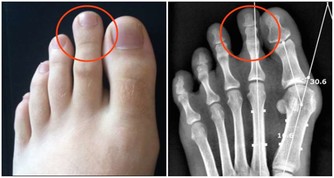

靜脈曲張。女性更容易出現這種情況,20歲後就有可能發生。一旦腿上的血管突然非常清晰,彎彎曲曲像蛇一樣,說明腿部血管出現了勞損。